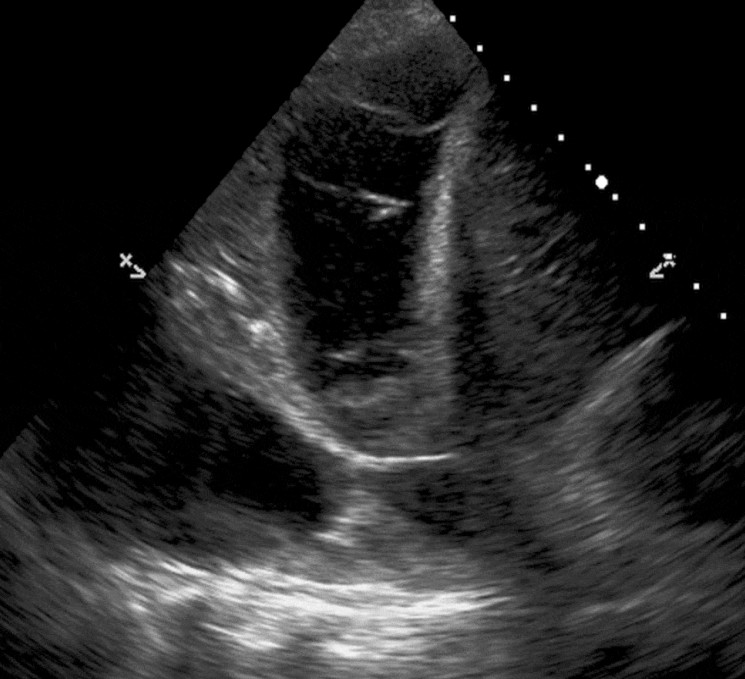

A view from your bedside ultrasound is shown.

2. Describe two relevant findings from the bedside ultrasound. 2 marks